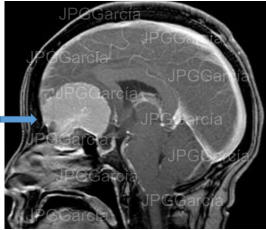

Meningioma del plano esfenoidal Imagen de resonancia magnética corte sagital